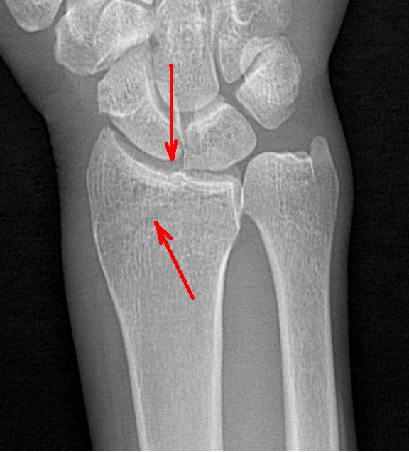

在常規(guī)拍片中,往往由于影像的重疊或體位等因素造成病灶部位漏診,而動態(tài)DR具有可視化功能,可以進(jìn)行動態(tài)觀察,毫秒級高清點片,更快捕捉到病灶點,大大降低漏診誤診幾率。比如,在常規(guī)拍片中易漏診的心臟后病灶、膈肌病變、隱匿肋骨骨折和小兒支氣管異物檢查等,在動態(tài)DR攝影中都有很高的確診率。

隱匿性骨折高清圖像